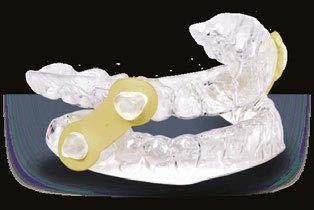

Here’s more good news. In this issue of Dental Sleep Practice, our Cover Story spotlights the latest in dental sleep medi cine solutions to treat OSA patients more effectively. SomnoMed’s second annual SomSummit focused on vetting the value of all sleep therapies and explored the fun damental research that supports them in improving, and even defining, OSA treat ment success. In our CE, “Interarch Jaw Registration Devices for Oral Sleep Appli ances,” Dr. Allen J. Moses explains bilat eral molar stabilization and creating a more open airway. In “Tongue Tie is Not Your Only

the patient that revealed symptoms of severe sleep bruxism, excessive daytime sleepiness, and snoring. The patient also complained of having chronic pain in the jaw and masseters, especially when waking up in the mornings. He reported gaining over 10 pounds in the last few years and the presence of hyperten sion which was not responsive to his daily medication.

The patient was referred to complete an in-lab polysomnogram (PSG) since it had been a long time since his previous sleep study.

The results of the PSG indicated the pres ence of severe OSA with an apnea/hypopnea index (AHI) of 43.1/Hr and respiratory dis turbance index (RDI) of 44.8/Hr. The PSG also indicated a REM dom inant OSA with an AHI of 58.6/Hr. The minimum SaO2 was 89.0% with a mean SaO2 of 98.8%. The sleep efficiency was cal culated at 93.4%.

Despite his severe OSA, the patient refused treatment with CPAP and was referred back to Dr. Yousefian’s office to be treated for his OSA and masticatory/temporoman dibular joint disorders (M/ TMJD). His treatment was initiated with bedtime use of the ApnoDent®, an FDA-approved oral appliance (Figure 2) designed to manage his bruxism, M/TMJD issues, snoring, and OSA.

An efficacy test was performed after four weeks of ApnoDent® use; the sleep test results indicated a reduction of AHI to 1.9/Hr with SpO2 nadir of 91%. The Mean SaO2 was 94.7%, and the sleep efficiency was 93.4%

The patient started his 2-year supervision phase and continued to use the ApnoDent

with a lower clear retainer at bedtime.